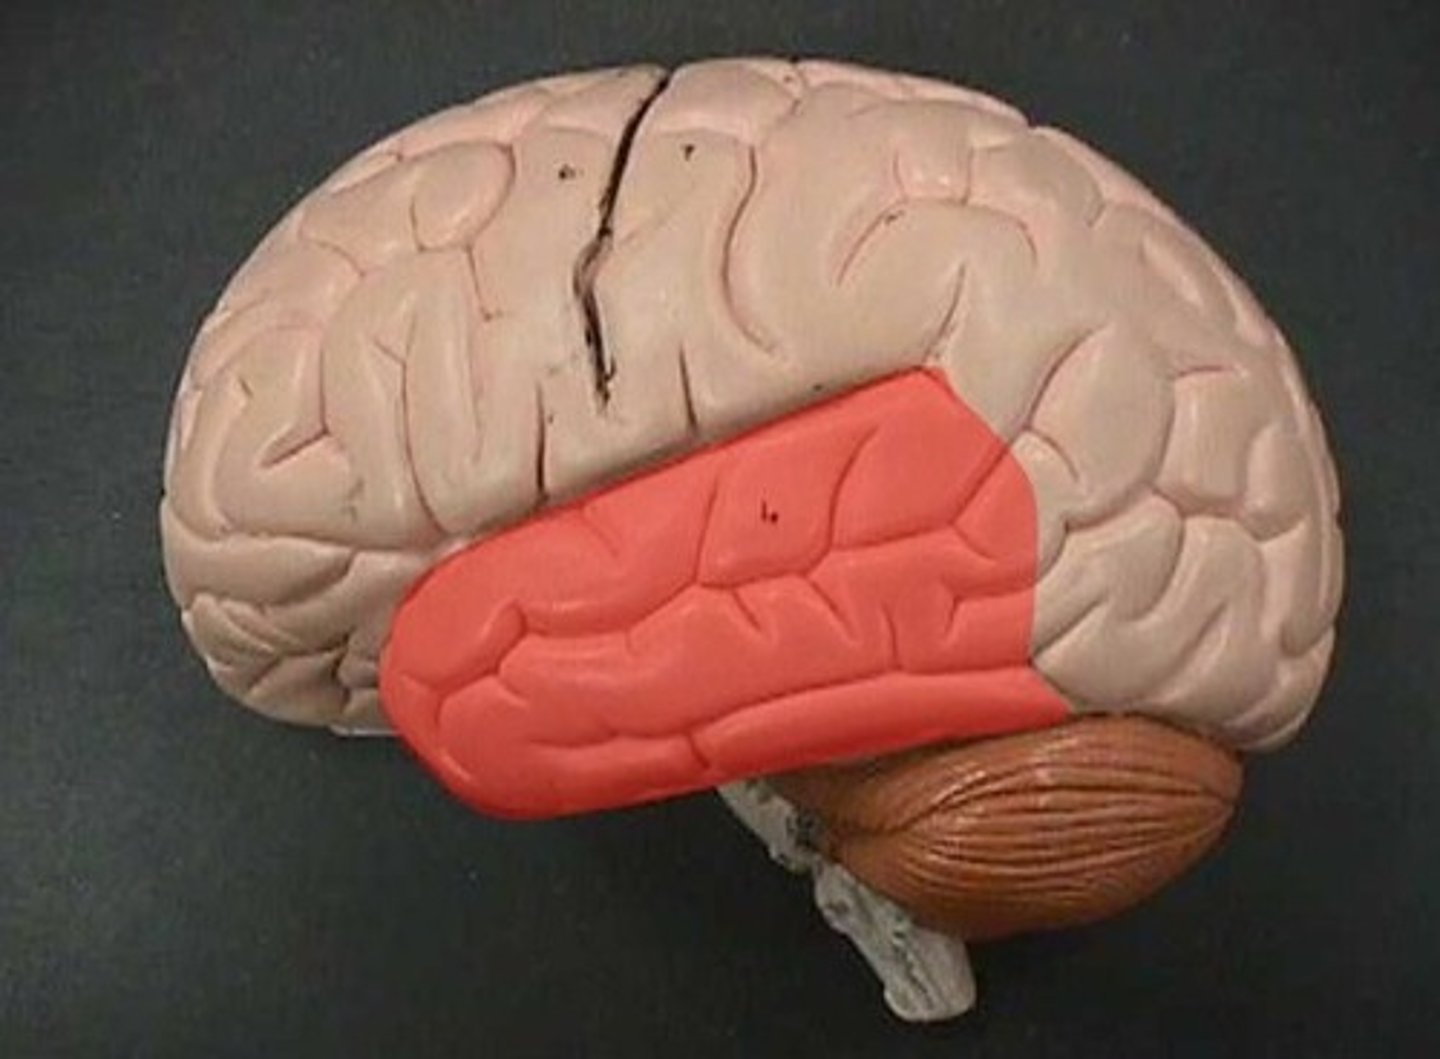

Temporal lobe

receives auditory information primarily from opposite ear